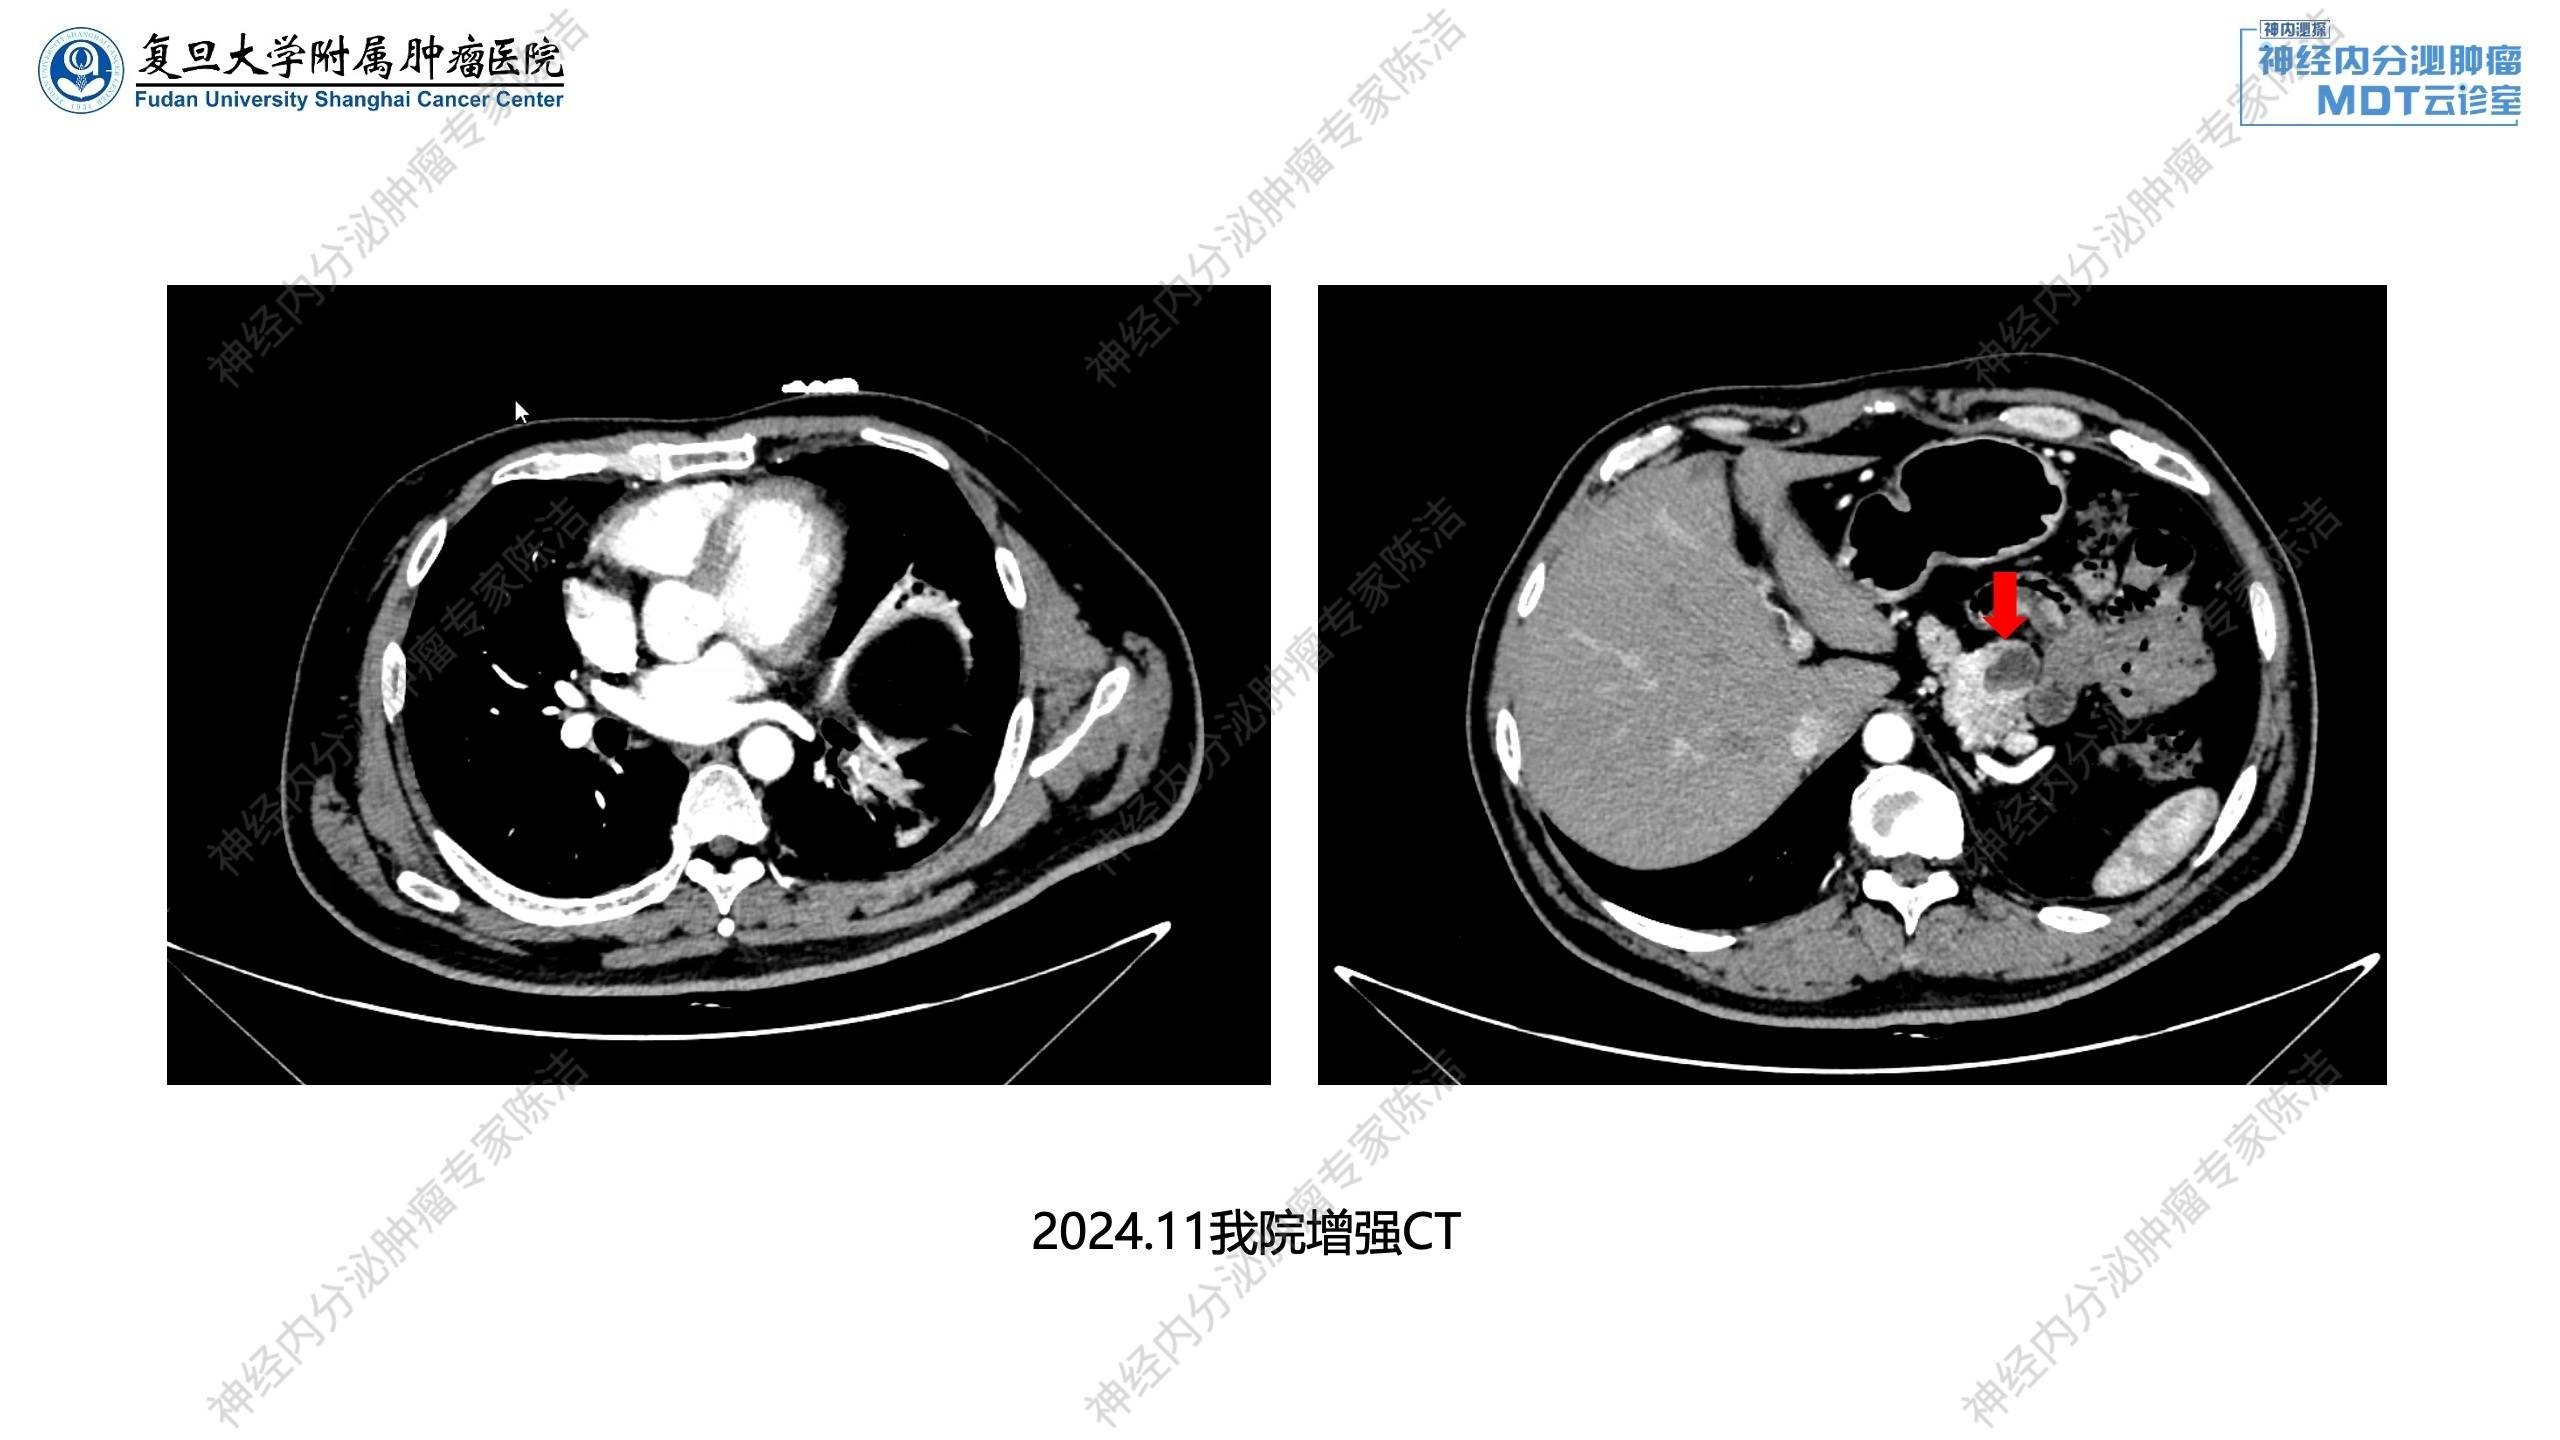

2024年11月:予完善相关激素检测,示垂体激素正常;胃泌素升高,PTH升高,血钙轻度升高。增强CT示胰腺多发囊实性占位;双肾小结石。

放射诊断科汤伟教授:腹部增强CT显示胰体部有一个比较大的富血供占位,中央伴有一些囊变。除此之外,胰头、胰体、胰尾还有多个富血供占位。这跟第一个病例比较相似,为多灶性胰腺神经内分泌瘤的改变。